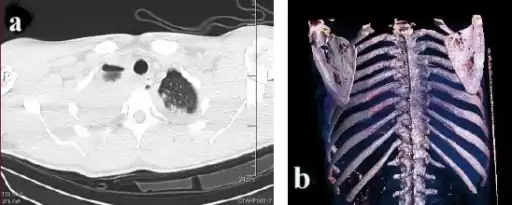

a)Axial computed tomography showing- bilateral scapular fractures (bilateral pulmonary contusion, left haemothorax) b) 3D computed tomography reconstruction shows bilateral scapular body fractures -